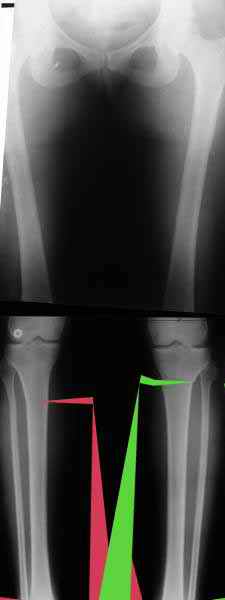

Из приведнной схемы не совсеим понял что означают разноцветные линии.

И зачем латерализация периферического фрагмента. Я всегда делаю медиализацию. См схему. И для данного случая медиализация подходит как нельзя лучше.

a> Я всегда делаю медиализацию. См схему. И для данного случая

Медиализация - это чисто эстетический прием, как я понимаю. Поскольку если делать остеотомию ниже вершины деформации, для восстановления оси надо делать смещение по ширине, в данном случае как раз латерализацию.

А вот на схемке без осей - там на разных уровнях (который правильнее?) устранение варуса чисто открытым клином без медиализации-латерализации. Если как-то так сделать - этого недостаточно будет?